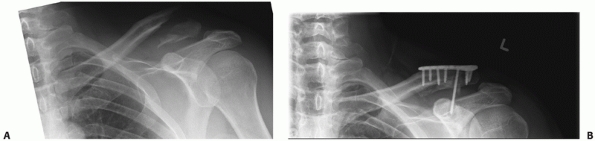

FIGURE 36-8 A.

Comminuted clavicle fracture resulting from a low-velocity gunshot wound with an associated hemopneumothorax and a retained intrathoracic bullet, treated with tube thoracostomy. The degree of clavicular deformity and the associated injuries represent a relative indication for operative repair. B. Severe injuries in a 25-year-old soldier struck by a high-velocity (AK-47) bullet that fractured the humerus, struck the clavicle, shattering the midportion, lacerated the subclavian vein and artery (causing life-threatening hemorrhage), and came to rest in the soft tissues of the neck. In an austere military operating environment, the clavicle fragments were resected and a vascular repair was performed.  |